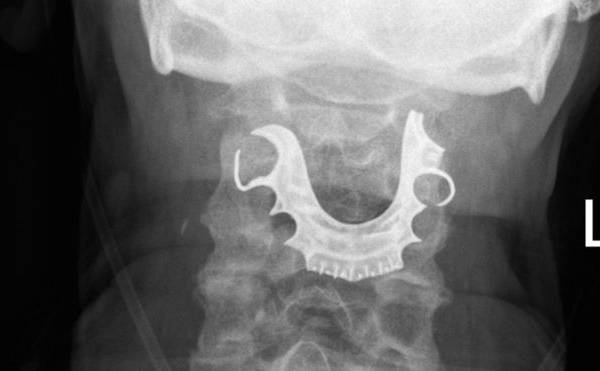

Los médicos encontraron la dentadura postiza del hombre en su laringe más de una semana después de operarlo.

Los médicos encontraron la dentadura postiza del hombre en su laringe.

Cuando el hombre regresó nuevamente dos días después, los médicos revisaron su garganta y fue entonces que encontraron un objeto semicircular sobre sus cuerdas vocales.

Y todo empezó a cobrar sentido cuando el hombre les contó que había perdido su dentadura postiza durante su operación.

Una vez que que le hallaron el objeto en la laringe, ocho días después de la primera operación, el paciente tuvo que ser intervenido nuevamente para remover la dentadura postiza de su cuerpo.